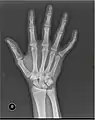

X-ray

X-ray image of right hand with thumb on left.

Multiple fractures of the metacarpals (aka broken hand). (Right hand shown with thumb on left.)